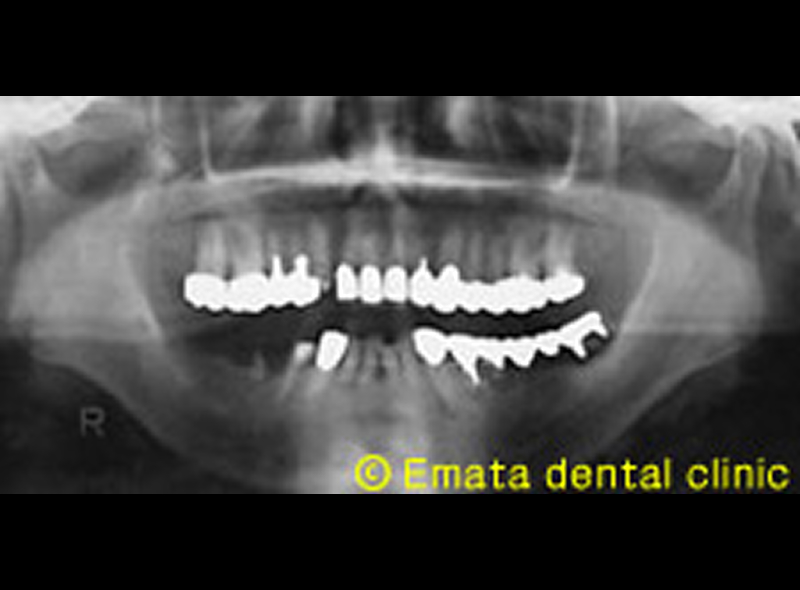

62歳 女性のケース

右下の奥歯が痛みと腫脹で来院されました。被せ物をはずして、洗浄し投薬しました。奥歯がなくよく噛めないのでこのさい全体的にしっかり治療したいということです。

患者さんは歯の欠損のほかにカリエス、根の病気、歯周病、噛み合わせの不調和などいろいろな問題があります。

レントゲン検査

デジタルパノラマレントゲンや10枚法などのさまざまな撮影方法を用いて、より詳細な歯や歯周組織の状態を把握するために用いられます。